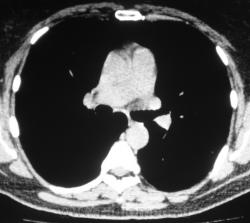

Произведена КТ.

КТ хотелось бы посмотреть в dicom-формате, меняя режимы, но на мой взгляд образование содержит известковые включения. Хотя, я не настаиваю, дождемся мнения коллег.

Нет "волшебных методов", можна поставить диф. ряд. Я бы дала такое заключение: хондрогамартрома, дифференцировать с туберкуломой, периферический рак менее вероятен. Можно жизнь прожить с гамартромой, а может озлиться в саркому. На практике был случай, когда лет 10 наблюдалась классическая скиалогически туберкулома, которая за полгода выросла и оказалась аденокарциномой. Таким образом, при любом раскладе, хирургическое лечение не является ошибкой, но решение об операции на легком должен принимать консилиум.

Дело не в желании, а в смысле. Что тут ещё можно сказать? На мой взгляд-мелкая, частично кальцинированная туберкулома.

Да, более туберкулёма.